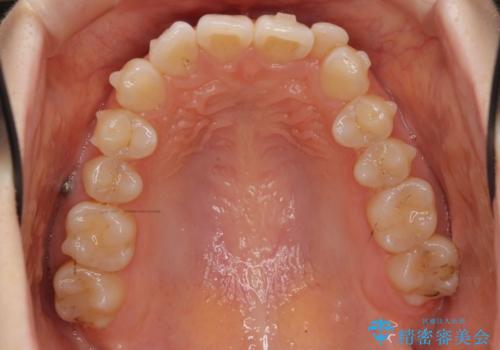

- 前歯の並びを主訴に来院。

マウスピースで歯を抜かずに治療しています。

左上の前歯が飛び出しており、唇が笑った時に引っかかっていたのが解消しています。

左上の前歯は小さいため、(矮小歯)左右対称になるようにセラミックで形を修正する治療も併用しています。

歯を大きくかぶせるスペースを作るため、右上の奥歯を後ろに下げています。

左にずれていた上の正中も揃い、大変喜んでいただきました。